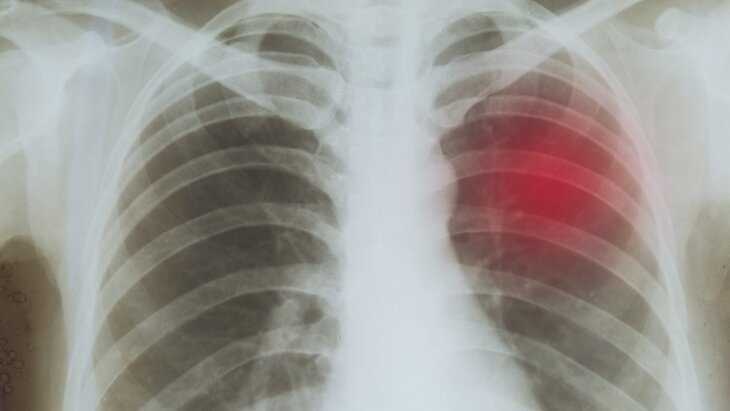

Новости здравоохраненияВ Подмосковье заболеваемость туберкулезом сократилась на 24,7%

В регионе снижается заболеваемость туберкулезом. С января по март 2026 года этот показатель составил 13,7 на 100 тысяч населения, рассказал главный врач Московского областного клинического противотуберкулезного диспансера Сергей Смердин. Его слова приводит пресс-служба регионального Минздрава.

В Подмосковье ведется серьезная работа по профилактике туберкулеза, его раннему выявлению и эффективному лечению. Благодаря этому показатель заболеваемости за три месяца 2026 года сократился на 24,7% по сравнению с аналогичным периодом 2025-го, заявил врач.